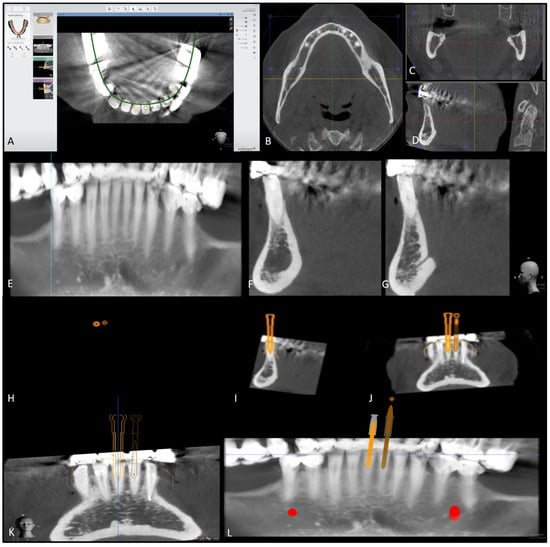

2. Case Report